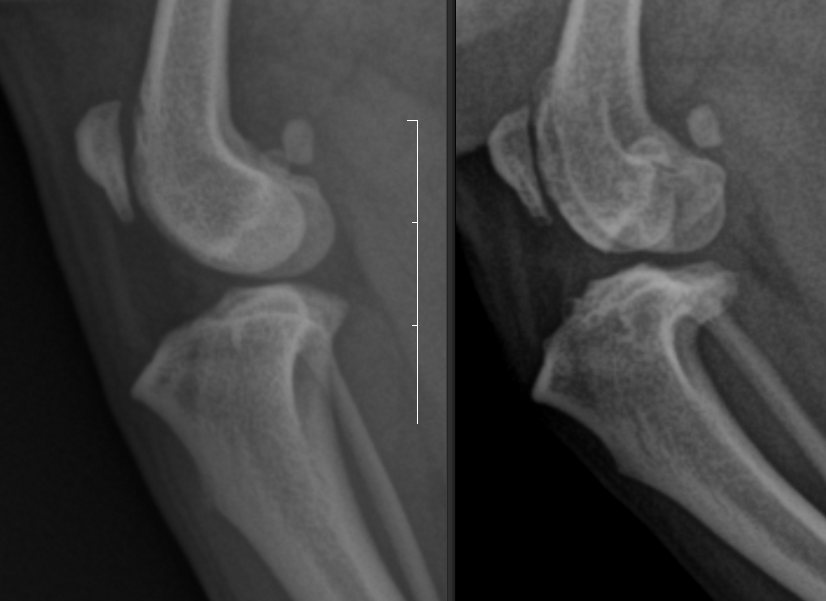

수술을 한 좌측 다리에서는 경미한 경골 조 면부 enthesophytosis가 관찰된다. 반면 수술하지 않은 우측 다리의 경우는 완전히 다른 예후를 보인다.

관절낭종창이나 관절의 심한 퇴행성 변화 양상은 차치하더라도 경골 조면의 후방의 골 증식양상이 뚜렷하며 이로서 경골의 TPL이 증가한 양상이 관찰된다. 이렇게 되면 십자인대에 가해지는 압력의 크기가 증가하여 십자인대가 파열할 가능성이 높으며 그 증거가 관절낭의 종창이다.